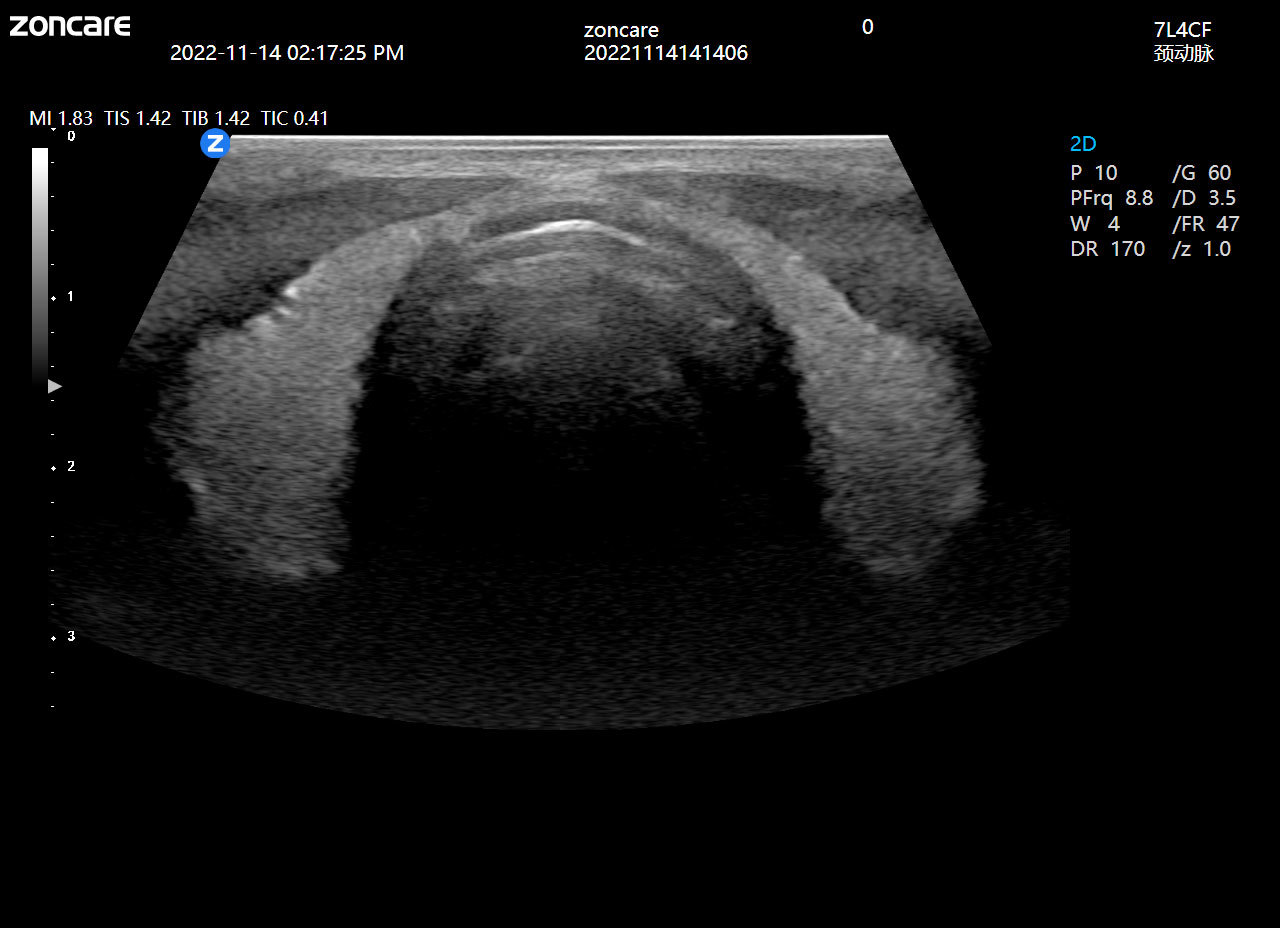

ViV95基于中旗全新的uSeed元数据极速成像技术平台,采用CPU+GPU双处理器异构计算技术,突破性解决了传统超声平台前端信号处理高损耗的技术难点,硬件电路集成度更高、性能更强、响应速度更快;同时,ViV95搭载新一代纯净波单晶探头和宽频带甲乳专用高频探头,可真实还原组织原貌,再现解剖细节。

优异的临床图像